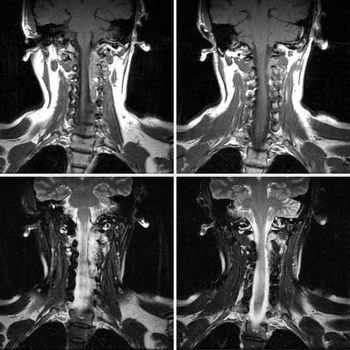

This case is a 26-year-old female in whom MRI imaging was done24 hours after an attempted hanging episode.